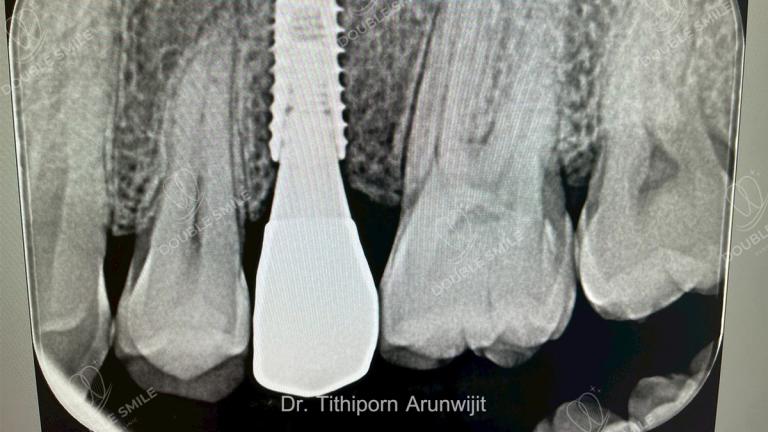

เคสรีวิวรากเทียม 17

Case Review

Before & After